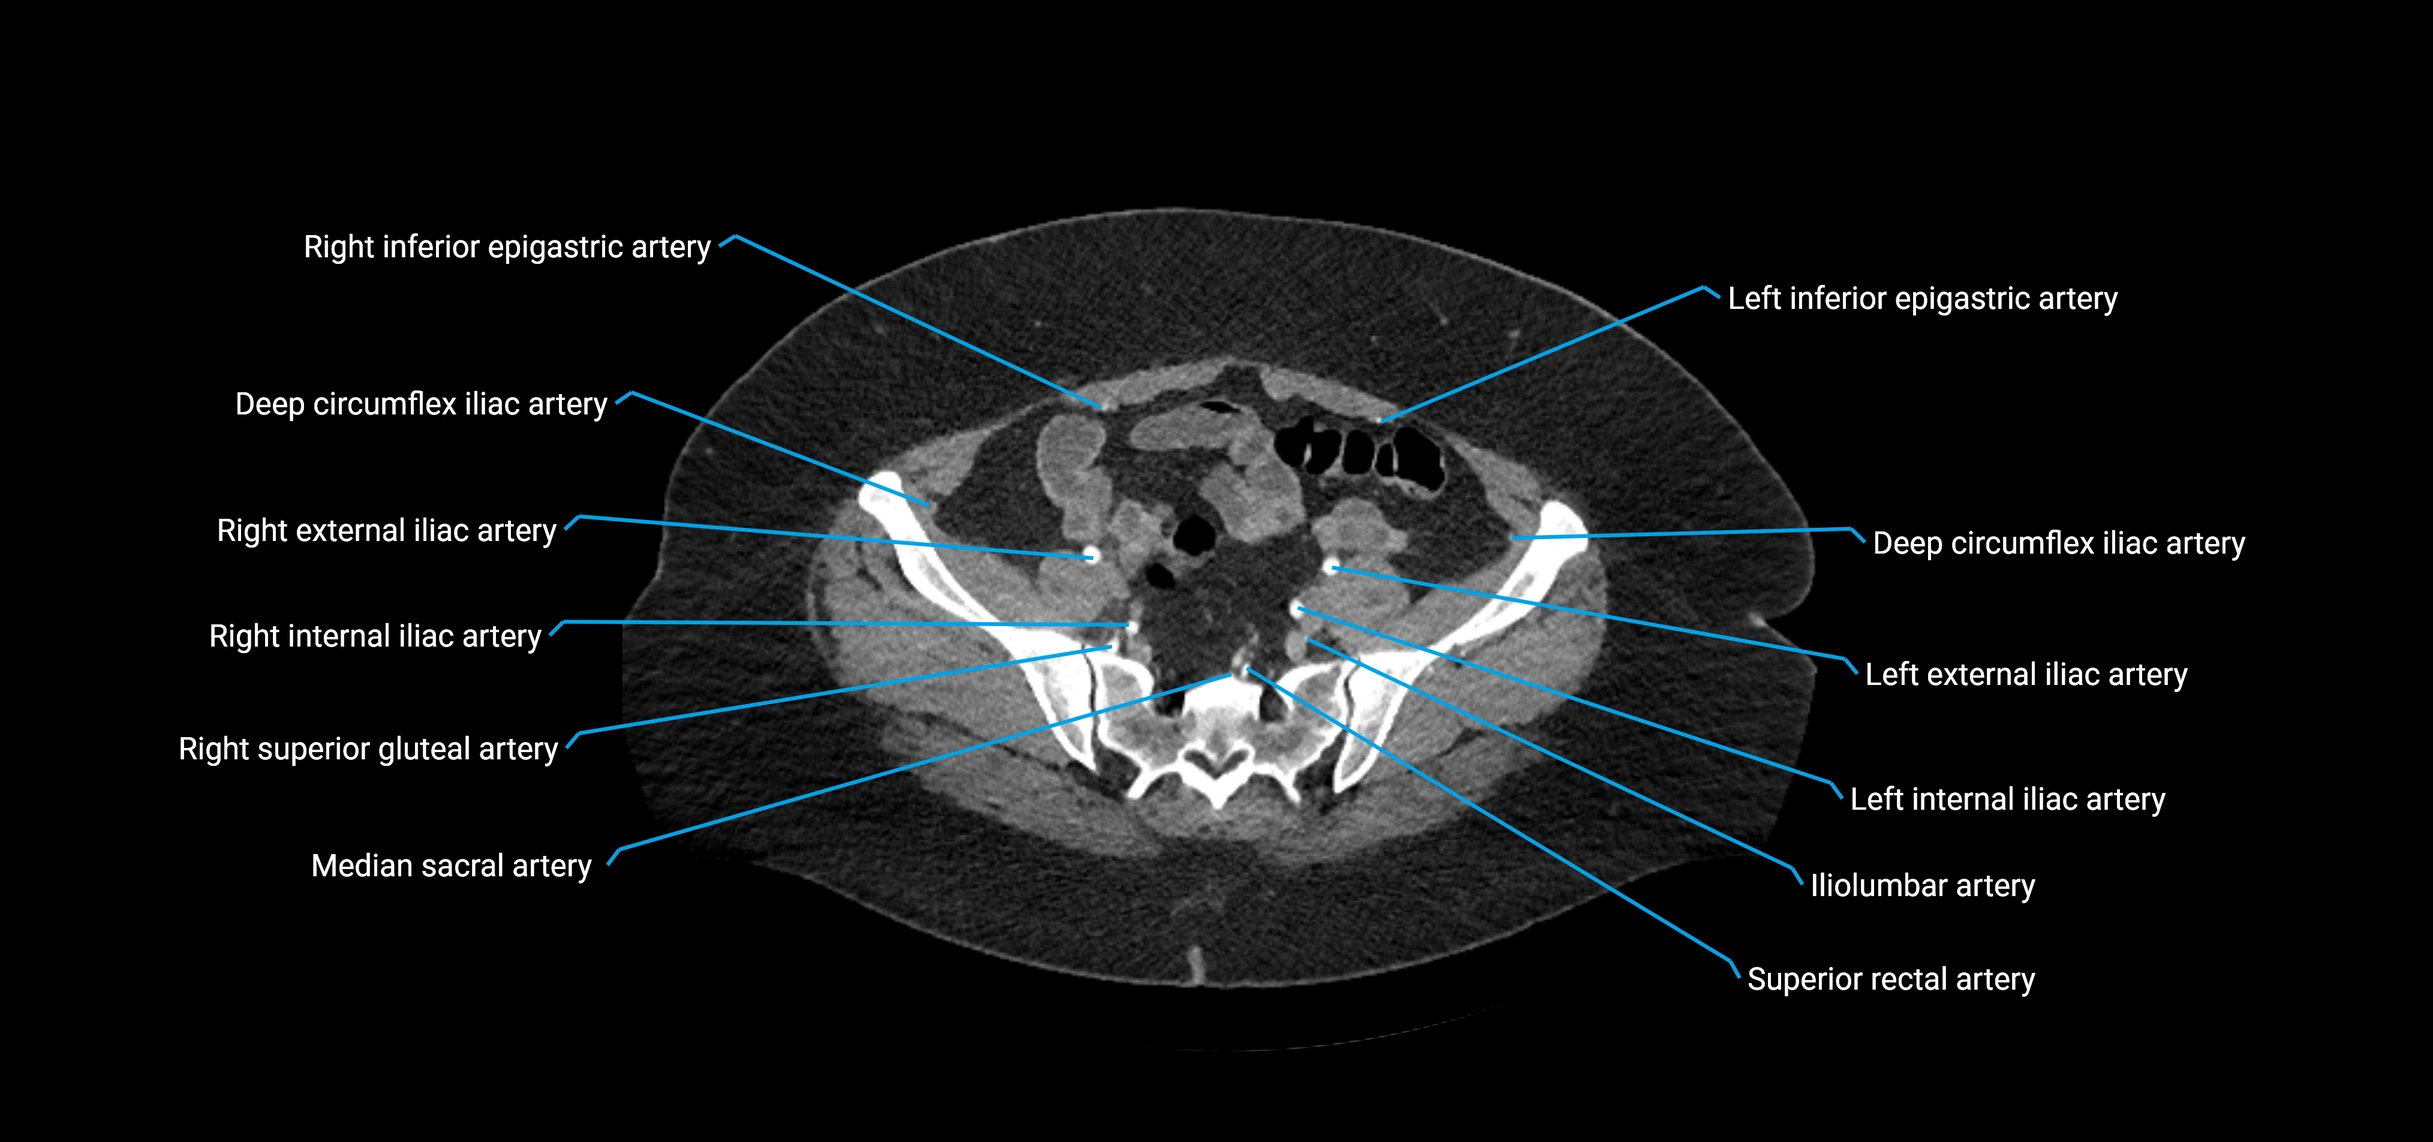

Contrast-enhanced CT (CTA):

• Gold standard for abdominal aortic imaging

• Provides excellent detail of lumen, wall, aneurysm, thrombus, and branch vessels

• Multiplanar and 3D reconstructions help in aneurysm measurement, stent graft planning, and dissection evaluation

• Detects acute rupture, traumatic injury, or occlusion with high sensitivity